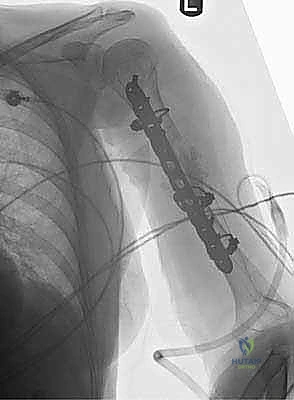

الحل الجراحي الأمثل: التثبيت بالشريحة والمسامير (Plate Osteosynthesis)

عندما يتخذ الأستاذ الدكتور محمد هطيف القرار الجراحي، فإن تقنية التثبيت بالشريحة والمسامير تُعد الخيار المفضل والمعيار الذهبي العالمي لعلاج معظم كسور جسم عظم العضد التي تتطلب جراحة.

تتفوق هذه التقنية على تقنية "المسمار النخاعي" (Intramedullary Nailing) في عظم العضد لعدة أسباب، أهمها تجنب إتلاف الكفة المدورة (Rotator Cuff) في مفصل الكتف، وتوفير رؤية مباشرة للعصب الكعبري لحمايته، وإمكانية تحقيق ضغط مباشر بين حواف الكسر (Absolute Stability) مما يسرع الالتئام.

أنواع الشرائح المستخدمة:

يستخدم الدكتور هطيف أحدث الشرائح الطبية المصنوعة من التيتانيوم النقي أو السبائك الطبية عالية الجودة، وتتضمن:

1. شرائح الضغط الديناميكي (DCP - Dynamic Compression Plates): صُممت بفتحات بيضاوية خاصة. عند إدخال المسمار، فإنه ينزلق في الفتحة ساحباً العظم معه، مما يولد ضغطاً هائلاً بين طرفي الكسر. هذا الضغط يلغي أي حركة ميكروية ويسمح بالالتئام العظمي الأولي (Primary Bone Healing).

2. الشرائح ذاتية الغلق (LCP - Locking Compression Plates): في هذه التقنية المتقدمة، تحتوي رأس المسمار على أسنان تُقفل (Lock) داخل الشريحة نفسها وليس فقط في العظم. هذا يخلق بنية ذات زاوية ثابتة (Fixed-angle construct)، وهي مثالية جداً في حالات هشاشة العظام حيث يكون العظم ضعيفاً ولا يتحمل المسامير العادية، أو في الكسور المفتتة بشدة.